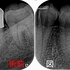

治療2回目

以前からある少し浮いている感じ、弱いジワ~とする痛みは残っているとのこと

基本的に長く続いていた症状は引くにも時間がかかることを説明し、根管内に問題が無ければ仕上げて行くと説明

根管充填+レジンコア+レジン充填まで

2026 EEdental YOA (5).jpg

レジン充填

2026 EEdental YOA (6).jpg

レジンである程度形を作りました。

術前⇒術中⇒術後

2026 EEdental YOA (7).jpg

術前の遠心ラインだと、オーバーカウントゥアーとレスカウントゥアーが存在していたのでその辺りも修正